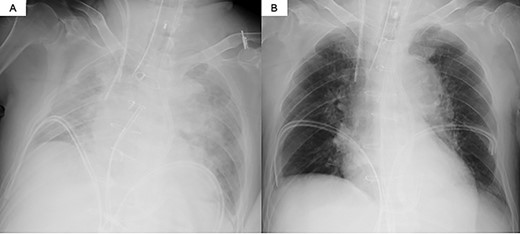

The decision was made to proceed first with PAB to stabilize the hemodynamics and delay the timing of surgical repair. After median sternotomy, PAB was attempted with a 4-mm wide Teflon felt band. The size of the band was adjusted to where the left to right shunt disappeared under transesophageal echocardiographic guidance (Fig. 1). Postoperative echocardiography revealed a bidirectional shunt through the VSR (Qp/Qs = 1.3), and the chest radiography showed decreased pulmonary congestion (Fig. 2). Cardiac output was maintained to allow adequate end-organ perfusion after PAB (urinary output >100 ml/h). Surgical VSR closure with the infarct exclusion technique and coronary artery bypass grafting were performed 7 days after PAB. The PAB was released after the initiation of cardiopulmonary bypass. Through the infarction area of the left ventricle, the right and left sides of the VSR and infarcted area were approached and covered with a bovine pericardial patch. No residual left to right shunt was observed on transesophageal echocardiography. On postoperative Day 32, the patient was discharged to a rehabilitation hospital.

Transesophageal echocardiography findings. (A) Pre-PAB; (B) post-PAB